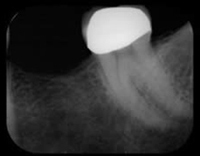

X-Rays and impressions (molds) are taken of the jaw and teeth to determine bone, gum tissue, and spacing available for an implant. While the area is numb, the implant will be surgically placed into the bone and allowed to heal and integrate itself onto the bone for up to six months. Depending on the type of implant, a second surgery may be required in order to place the "post" that will hold the artificial tooth in place. With other implants the post and anchor are already attached and placed at the same time.

First step to surgically place the implant in the bone